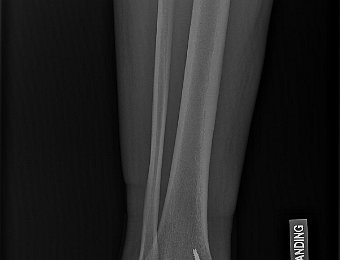

PreOp

10 images